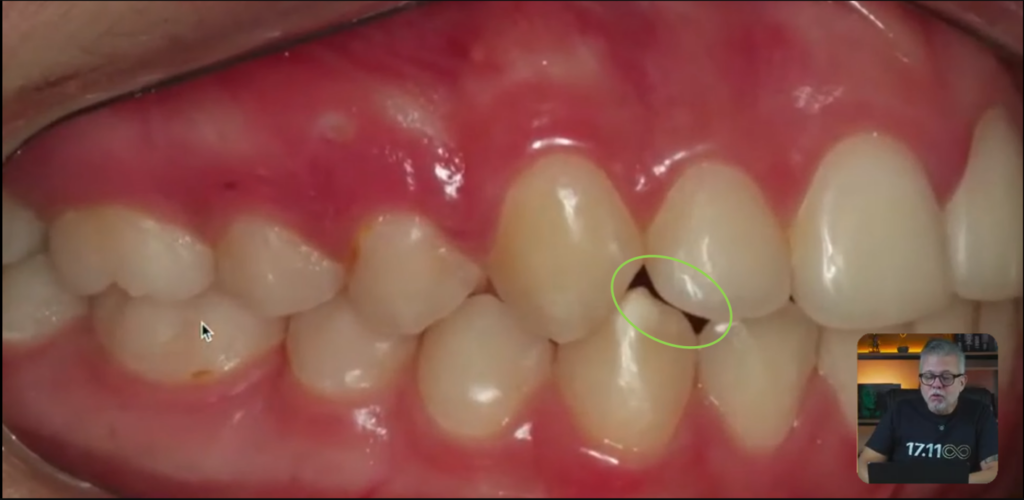

Alguns detalhes como, vejam que parece que tem um espaço escurecido aqui no incisivo lateral:

Por que ficou assim, professor?

Anatomia do dente.

Hélio, o que mais que tem de problema?

Olha o zênite desse lateral e olha desse lateral aqui:

Vocês estão vendo esse canino aqui, que tem um espacinho aqui atrás:

Quando esse paciente pega essa mandíbula dele, os dentes inferiores, e ele faz o movimento de lateralidade, esse canino inferior, pessoal, ele não toca imediatamente no canino superior.

Então, não faz a desoclusão imediata.

Todo caso que você terminar tem que fazer a desoclusão imediata, porque senão os dentes posteriores vão ficar com um contato ou então um movimento no sentido látero-lateral.